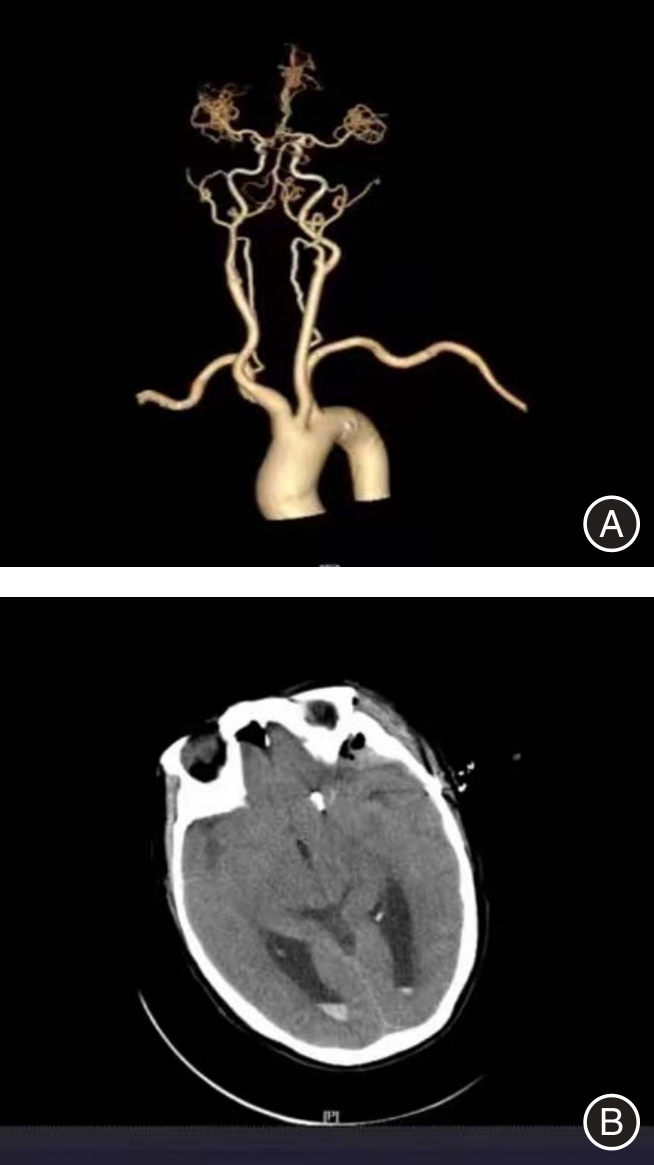

目的 探讨血清基质金属蛋白酶2(MMP-2)、髓过氧化物酶(MPO)、神经轴突导向因子3E(Sema3E)对全麻颅内动脉瘤夹闭术患者预后的预测价值。 方法 选取2023年5月至2025年5月张家口市第一医院收治125例全麻颅内动脉瘤夹闭术患者作为研究对象,根据术后1个月格拉斯哥预后评分(GOS),将1 ~ 3分的患者纳入预后不良组(29例),4 ~ 5分的患者纳入预后良好组(96例)。比较两组临床资料及血清MMP-2、MPO、Sema3E水平,并予以多因素logistic回归分析法分析全麻颅内动脉瘤夹闭术患者预后不良的危险因素,采用受试者工作特征(ROC)曲线分析血清MMP-2、MPO、Sema3E对全麻颅内动脉瘤夹闭术患者预后的预测价值,比较不同临床特征血清MMP-2、MPO、Sema3E水平,采用Spearman相关性分析血清MMP-2、MPO、Sema3E与临床特征的相关性。 结果 预后不良组Hunt-Hess分级Ⅲ级、术前GCS评分< 8分的患者占比为27.59%、51.72%,高于预后良好组的10.42%、5.21%(P < 0.05)。预后不良组血清MMP-2、MPO、Sema3E水平均高于预后良好组(P < 0.05)。血清MMP-2、MPO、Sema3E水平高是全麻颅内动脉瘤夹闭术患者预后不良的独立危险因素(OR = 1.087、2.807、2.079,P < 0.05)。血清MMP-2、MPO、Sema3E及联合检测预测全麻颅内动脉瘤夹闭术患者预后的曲线下面积(AUC)分别为0.747、0.690、0.656、0.809,诊断敏感度分别为72.41%、62.07%、68.97%、86.21%,特异度分别为72.92%、73.96%、66.67%、70.83%,其中联合检测的AUC最高(P < 0.05)。Hunt-Hess分级Ⅲ级患者血清MMP-2、MPO、Sema3E水平高于Ⅰ级、Ⅱ级患者,Ⅱ级患者高于Ⅰ级患者;术前GCS评分< 8分的患者血清MMP-2、MPO、Sema3E水平高于≥ 8分的患者(P < 0.05)。血清MMP-2、MPO、Sema3E与Hunt-Hess分级均呈正相关(r= 0.497、0.662、0.595,P < 0.05),与术前GCS评分均呈正相关(r = -0.547、-0.602、-0.697,P < 0.05)。 结论 全麻颅内动脉瘤夹闭术患者Hunt-Hess分级及术前GCS评分与预后具有一定联系,且血清MMP-2、MPO、Sema3E水平与Hunt-Hess分级、GCS评分密切相关,血清MMP-2、MPO、Sema3E水平高均为全麻颅内动脉瘤夹闭术患者预后不良的独立危险因素,且对患者预后具有较高预测价值,其中联合检测的预测价值最高。

Objective To explore the predictive value of serum matrix metalloproteinase-2 (MMP-2), myeloperoxidase (MPO), and axonal guidance factor 3E (Sema3E) in predicting the prognosis of patients undergoing intracranial aneurysm clipping surgery under general anesthesia. Methods A total of 125 patients who underwent general anesthesia for intracranial aneurysm clipping surgery at Zhangjiakou First Hospital from May 2023 to May 2025 were selected as the study subjects. Patients with Glasgow Outcome Scale (GOS) scores ranging from 1 to 3 one month after surgery were included in the poor prognosis group (29 cases), while those with scores from 4 to 5 were included in the good prognosis group (96 cases). The clinical data and the levels of serum MMP-2, MPO, and Sema3E were compared between the two groups. Multivariate logistic regression analysis was used to analyze the risk factors for poor prognosis in patients undergoing general anesthesia for intracranial aneurysm clipping surgery. Receiver Operating Characteristic (ROC) curves were employed to analyze the predictive value of serum MMP-2, MPO, and Sema3E for the prognosis of patients undergoing intracranial aneurysm clipping under general anesthesia. The levels of serum MMP-2, MPO, and Sema3E among patients with different clinical characteristics were compared. Spearman correlation analysis was conducted to investigate the correlation between serum MMP-2, MPO, and Sema3E and clinical features. Results The proportions of patients with Hunt-Hess grade Ⅲ and preoperative Glasgow Coma Scale (GCS) score < 8 in the poor prognosis group were 27.59% and 51.72%, respectively, which were higher than the 10.42% and 5.21% in the good prognosis group (P < 0.05). The levels of serum matrix metalloproteinase-2 (MMP-2), myeloperoxidase (MPO), and semaphorin 3E (Sema3E) in the poor prognosis group were higher than those in the good prognosis group (P < 0.05). High levels of serum MMP-2, MPO, and Sema3E were independent risk factors for poor prognosis in patients undergoing intracranial aneurysm clipping surgery under general anesthesia (OR = 1.087, 2.807, 2.079, P < 0.05). The areas under the curve (AUC) for predicting the prognosis of patients undergoing intracranial aneurysm clipping surgery under general anesthesia using serum MMP-2, MPO, Sema3E, and combined detection were 0.747, 0.690, 0.656, and 0.809, respectively. The diagnostic sensitivities were 72.41%, 62.07%, 68.97%, and 86.21%, and the specificities were 72.92%, 73.96%, 66.67%, and 70.83%, respectively. Among them, the AUC of combined detection was the highest (P < 0.05). The levels of serum MMP-2, MPO, and Sema3E in Hunt-Hess grade Ⅲ patients were higher than those in grade Ⅰ and Ⅱ patients, with grade Ⅱ patients having higher levels than grade Ⅰ patients. Patients with preoperative GCS scores < 8 had higher levels of serum MMP-2, MPO, and Sema3E than those with scores ≥ 8 (P < 0.05). Serum MMP-2, MPO, and Sema3E were positively correlated with Hunt-Hess grading (r = 0.497, 0.662, 0.595, 0.639, P < 0.05) and negatively correlated with scores of preoperative GCS (r = -0.547, -0.602, -0.697, -0.521, P < 0.05). Conclusions There was a certain correlation between Hunt-Hess grading, preoperative Glasgow Coma Scale (GCS) score, and the prognosis of patients undergoing intracranial aneurysm clipping surgery under general anesthesia. The levels of serum matrix metalloproteinase-2 (MMP-2), myeloperoxidase (MPO), and semaphorin 3E (Sema3E) were closely related to Hunt-Hess grading and GCS score. High levels of serum MMP-2, MPO, and Sema3E were independent risk factors for poor prognosis in patients undergoing intracranial aneurysm clipping surgery under general anesthesia and had high predictive value for patient prognosis. Among them, combined detection had the highest predictive value.